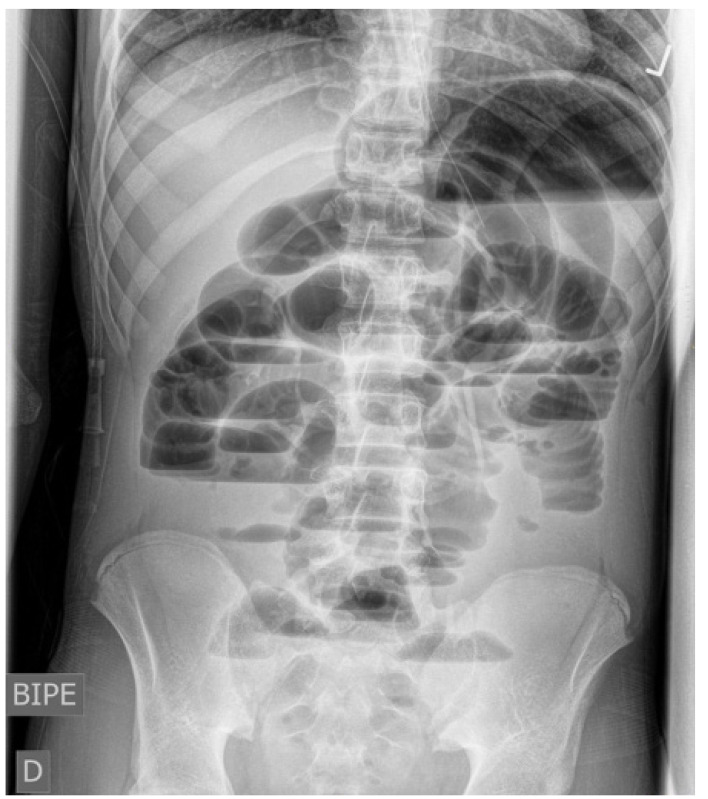

Abdominal internal hernia is a rare cause of intestinal obstruction in pediatric emergency departments, being the herniation through the foramen of Winslow an exceptional entity (less than 0.5% of the herniae). We report the case of a 15-year-old adolescent male without previous surgical interventions who presented with abdominal pain and vomiting; computed tomography scans showed intestinal obstruction due to an internal hernia through the foramen of Winslow. To reduce the herniated ileum, the patient required surgical intervention with diagnostic laparoscopy, which, due to bad visualization, was changed to supraumbilical midline laparotomy. There was no need to resect the affected ileum as it appeared healthy. We did not perform a preventive technique to reduce the risk of recurrence. Postoperative pelvic collection was conservatively managed with antibiotics. The patient undergoes regular follow-up in the pediatric surgery department.